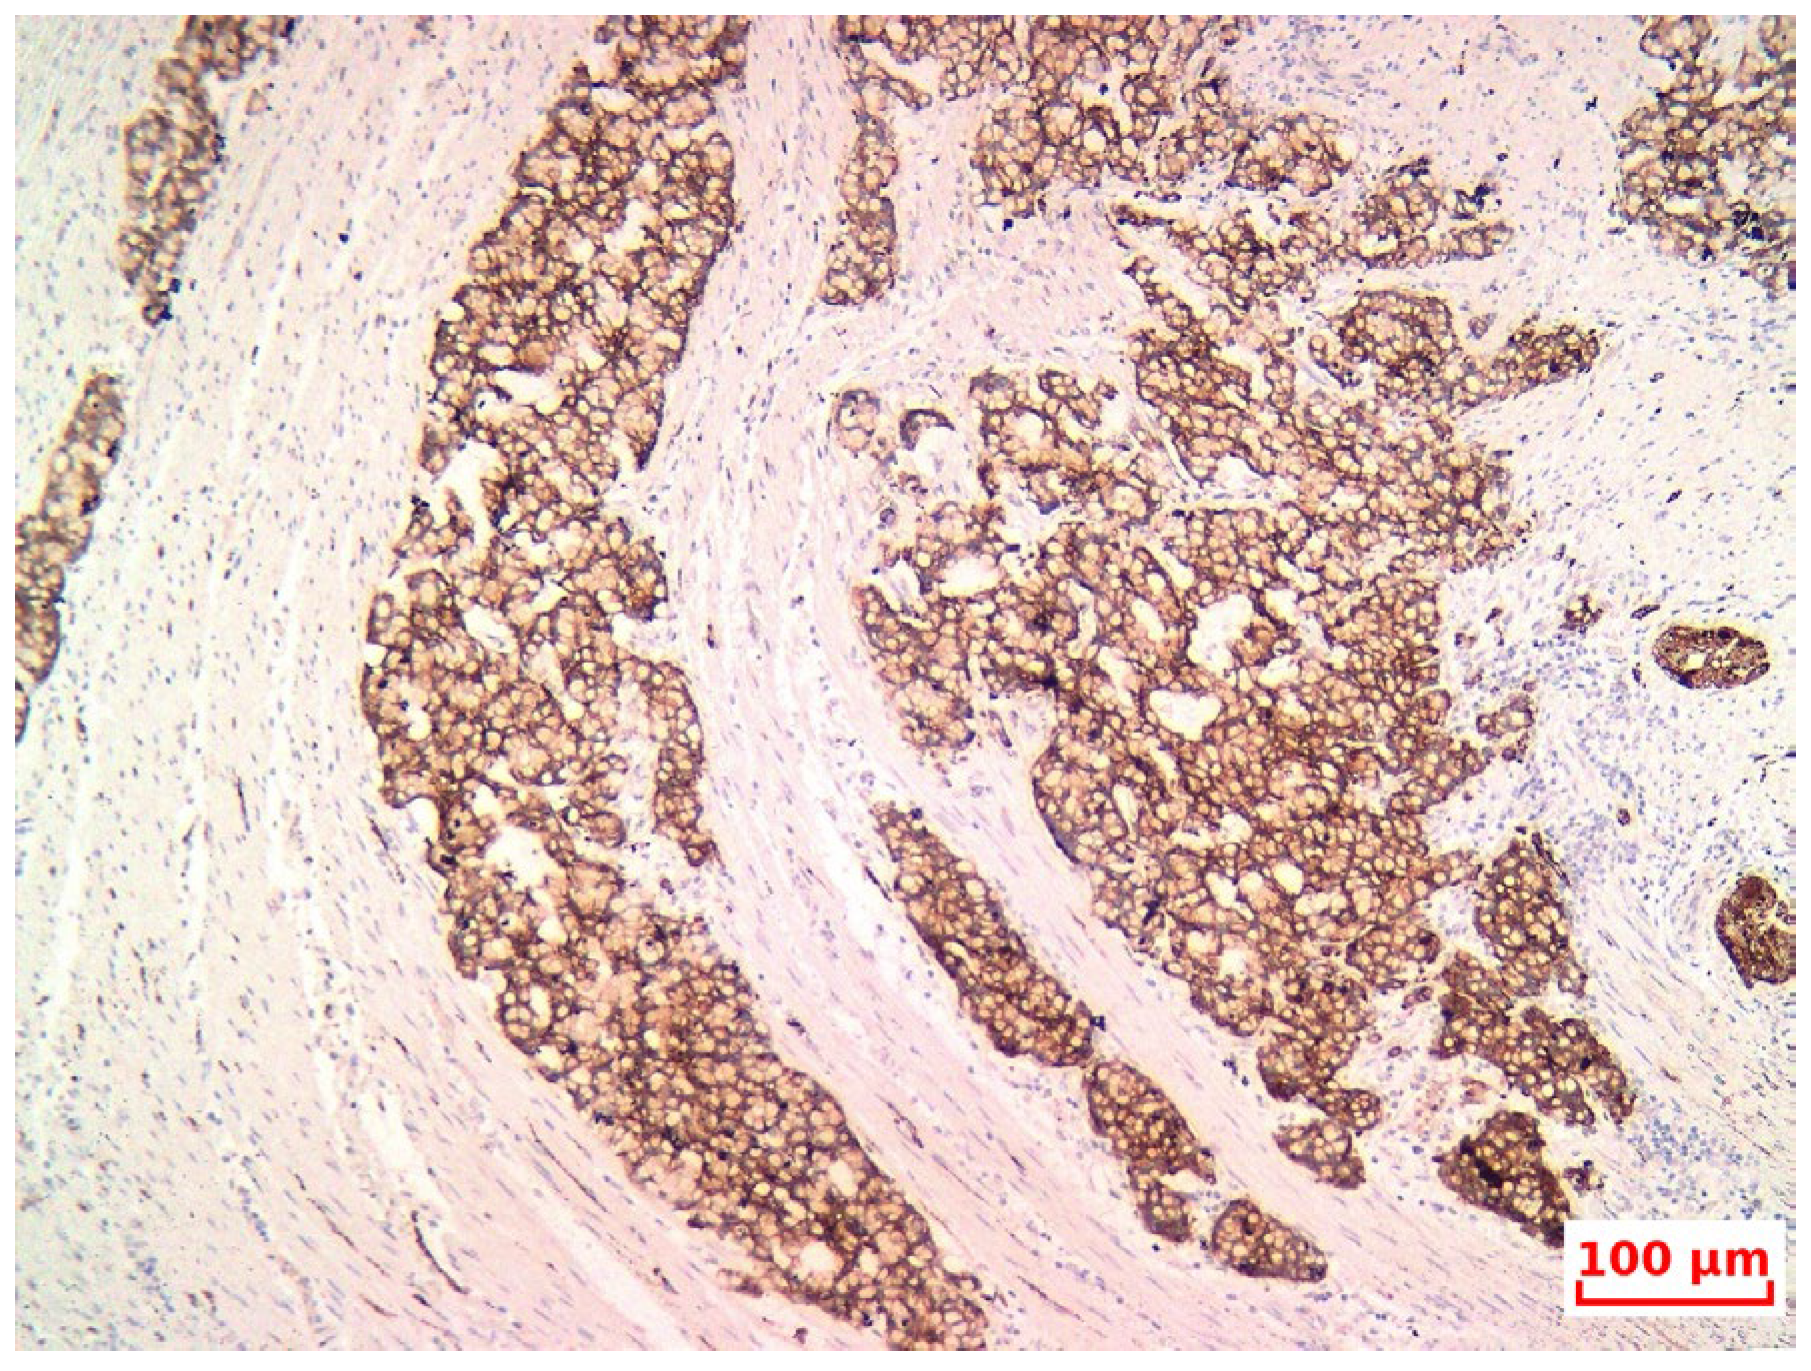

- The diagnosis of GCA was confirmed based on its characteristic histopathological features, and the non-endocrine component was verified through immunohistochemistry (IHC), although this may erroneously lead pathologists toward a NET diagnosis. Therefore, subspecialty pathology review of appendiceal neoplasms at referral centers is warranted, as emphasized by Jedrkiewicz [25].

- Diagnostic pitfalls: Goblet cell adenocarcinoma (GCA) often presents with overlapping histological features of both adenocarcinoma and neuroendocrine tumors, which can lead to misclassification as typical carcinoid or mixed adenoneuroendocrinecarcinoma (MANEC). The diagnosis requires awareness of the dual phenotype, with both glandular (mucin-secreting) and neuroendocrine features, best demonstrated by morphology and immunohistochemistry (e.g., synaptophysin/chromogranin A positivity with Ki-67 > 20% in high-grade cases).

- Differentiation from MANEC and typical carcinoids: According to the 2019 WHO classification, GCAs are considered distinct from MANECs, as they represent a unique histologic and molecular entity. Unlike classical NET G1/G2 carcinoids, GCAs tend to be more aggressive, display infiltrative growth, and have a higher proliferative index.